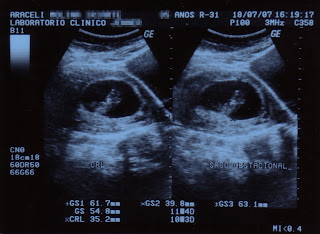

En esta ocasión quiero presentaros a alguien, que si Dios quiere se unirá a la familia a mediados de febrero. Esta semana nos ha pegado un buen susto, porque quería llegar antes; pero gracias a Dios, Araceli ya está bien y posiblemente mañana regrese a casa.

Y sin más dilación, os presento a Josué.

Este ultrasonido es de cuando tenía 10 semanas, lo siento. Ayer le hicieron otro, pero en consulta no nos lo dan, así que tendremos que esperar un poquito para tener una foto reciente —quizá el finde, no sé, según nos diga el médico—. En cuanto la tengamos, la cuelgo aquí.

Saludos.

Nota: No hay ninguna duda sobre su sexo... el sinvergüenza incluso abría las piernas para que la doctora lo viera bien.

Nota 2: Bueno, al menos no hizo como Bart Simpson...